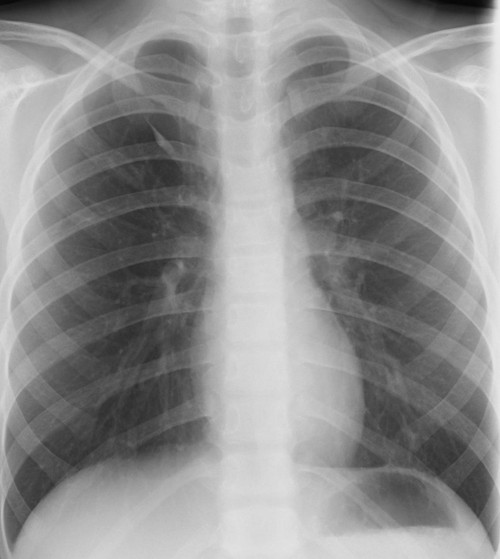

もう一段上級を目指す胸部X線診断は腫瘤影を探してみ見えない肺癌を読み取ることであり、腫瘤影の存在を探すのではなく、腫瘤が存在することによる付属所見を見つけることである。漫然と見ていても、自然と目に入ってくる所見ではなく、こちらから存在することが異常であるとの認識で付属所見を探しに行くことが必要である。

そして変化部位を探すことが必要で、そのためには、比較読影が必要である。

レントゲンでも同様であるが、以前の写真があれば、その比較が簡単にできるが、以前の写真がない場合には、比較ができない。そのため、自分の頭の中に比較のための受け皿を作っておく必要がある。

そのためには正常とCTで診断された百枚のレントゲンを細かく所見を見ていき、単純写真で異常所見かもと疑った部位をCT画像で確認し、どうして異常所見と判断したかを確認していけば、正常のバリエーションか異常かの判断ができるようになると信じている。

読影上見落としやすいレントゲン部位は、正常構造で重なりがある部分であり、そういう場、異常があるものだと思って読影することも必要である。